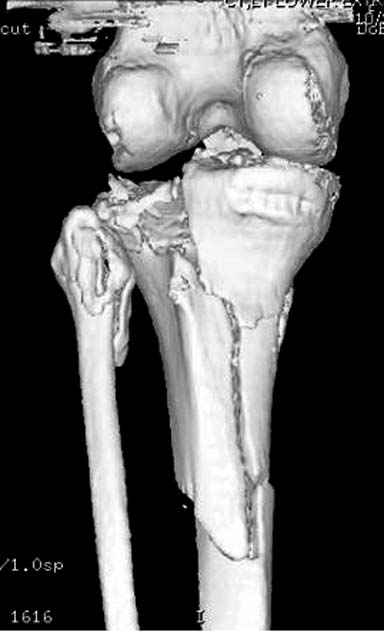

Способ фиксации сам по себе - вполне приемлемый. Однако фиксации должна предшествовать репозиция.

Боюсь, задача восстановления формы суставной поверхности tibia осталась нерешенной.

Имелась центральная компрессия. Проводилась артротомия - суставная линия полностью восстановлена. Произведу контрольные рентгенограммы для доказательства.

Спасибо заранее, с интересом посмотрим. Хорошо бы КТ сделать.

Для адекватной оценки необходимо предоставить хотя бы по две проекции до и после синтеза. Снимки после синтеза - с захватом всей длины сегмента т.к. использовался гвоздь. По предоставленной одной некачественной проекции сказать можно только сказать что и решение, и результат спорные.

Отдельные переломы тибиал плато и перелом проксимальной трети большеберцовой кости отличаются от переломов тибиал плато с вовлечением диафиза. Здесь перелом тибиал плато типа Schatzker VI, полученный в результате высокоэнергетической травмы. Перелом метафиза образовал отрыв суставной поверхности от диафиза с вовлечением медиального и латерального мыщелков. Двухмыщелковые переломы из-за укрочения опасны развитием компартаментального синдрома, повреждением латерального мениска и связок.

Суббота, суббота! Море, как обманчиво кажется каждым утром выходного дня, свободного времени впереди и можно попытаться объяснить, какой смысл заключается в моём на бегу брошенном мнении, для краткости сформулированном ёмко и однозначно: «говно». Так вот, никакого такого иного, тайного, облегчённого и скрытого смысла в этом жизнеутверждающем и более широком, нежели любой из медицинских терминов слове нет и быть не может. Более того, определённый опыт (если хотите, профессиональная интуиция) подсказывает мне, что если Владимир представит и обязательную вторую, обязательную, и качественную и длинную достаточно рентгенограмму, это не изменит вышеприведённой характеристики. Если не наоборот. Я уже не говорю о КТ. Ибо хорошо упакованные продукты жизнедеятельности ими же и остаются. Качественный состав не меняется. При этом это ни в коей не относится к Вам лично, Владимир. Так я позволил себе охарактеризовать вывешенный Вами результат хирургии в ответ, подчеркну, на Ваш же запрос. Естественно то, к сожалению, подчеркну, естественно, что каждый из нас продуцирует не только блестящие результаты. И чем больше работаешь, тем критичнее к своим случаям стараешься относиться. Ну, хотелось бы, во всяком случае, думать, что это именно так. Но, в нашем случае мы имеем дело не со случайностью и технической помаркой. В данном случае мы имеем дело с ПРОГРАММИРОВАНИЕМ не блестящего результата. И не в комбинации имплантатов дело. Я совершенно не противник комбинирования и сам не часто, но использую это. Приходится, так как и архитектоника перелома иногда заставляет, и экономика может диктовать. Конечно, с моей точки зрения 41С3.3. (или Шацкер 6) не лучшая платформа для такого комбинирования, но, подчеркну, не в этом дело. Или не только в этом. В другом. В Вашей оценке ситуации до операции и в предоперационном планировании, прежде всего. Говорят: „failing to plan means planning to fail“. На русском не так чётко и чуть длиннее, но суть остаётся той же: «Провальный предоперационный план есть не что иное, как планирование хирургического провала». Мне не хочется анализировать каждый из введённых Вами винтов (болтов-стяжек?, что и куда там торчит…), хотя КАЖДЫЙ из этих имплантатов должен нести смысловую нагрузку. Давайте попробуем разобраться, как дОлжно делать, ну а выводы, как всегда, каждый делает сам.

И так, высокоэнергетическая травма – это, прежде всего, тяжёлое повреждение мягких тканей со сломанной костью внутри. Относится ли данное утверждение к переломам плато? И да, и нет. Значительная часть наших пациентов с переломами плато – это люди пожилого и старческого возраста с низкоэнергетической травмой. Как правило, это низкоэнергетические повреждения с отсутствием контузии, фликтен, то есть хорошим состоянием мягких тканей, где в результате перелома нарушена, прежде всего, механическая ось конечности. Мягкие ткани позволяют оперировать нам такие переломы в ранние сроки. Но, главная проблема, с которой мы сталкиваемся здесь – это проблема фиксации порозной кости. Вот здесь и уместны блокируемые имплантаты (благо, в отличие от нашей работы 10-15 лет назад, сейчас и продукта данного, и производителей на рынке предостаточно в разном ценовом диапазоне). Имплантаты прежних генераций здесь используются с трудом, нужно хорошо знать классическую технику, пользоваться пластикой, не забывать о том, что банальный костный цемент может быть реальной «палочкой-выручалочкой». Но, в нашем случае – другая история. Это высокоэнергетическая травма. И здесь как раз сломанная кость внутри повреждённых мягких тканей. Здесь как раз и доступы, и время, подходящее для операции, и технологии – всё сплетается в один клубок, распутать который нам и помогает нормальный предоперационный план. И так, в случае высокоэнергетического перелома тибиального плато мы сталкиваемся с тяжёлым повреждением мягких тканей, контузиями, фликтенами, риском развития компартмент-синдрома, зачастую переломы носят открытый характер и в своих крайних составляющих сопровождаются повреждением и сосудов, и нервов. Поэтому вначале мы лечим мягкие ткани – то бишь создаём комфортные условия для них. Это может быть шинирующий наружный фиксатор, это может быть и более многими любимый аппарат Илизарова. Условие одно – избегать гипердистракции, это плохо для мягких тканей и даже может способствовать развитию компартмент-синдрома. Мягким тканям должно быть «уютно» в этот непростой для всей конечности период и беспокоить их лишний раз в это тяжёлое время не нужно. Иногда – а это зависит от структуры перелома, стабильности отломков и тяжести повреждения мягких тканей даже хорошо смягчённая, в положении лёгкого сгибания в коленном суставе, очень свободная внешняя повязка сгодится – полимерная или даже гипсовая. Иногда – только дисциплинирующее лёгкое скелетное вытяжение. Главное, если нет компартмента – не трогай! Ждём. И стараемся оперировать в оптимальные сроки, диапазон которых здесь достаточно широк – от 5-6 до 21-23 дней с момента травмы. Морщинки на коже лучше всего подскажут нам это время. Однако, время впустую не теряем – мы обследуем больного и, не побоюсь этого слова, думаем даже, и обсуждаем с нашей бригадой пре-план. Что нам нужно из обследования? КТ – идеально. Однако, что скрывается за утверждением: «КТ – золотой стандарт в обследовании всех пациентов с внутрисуставными переломами»? Ведь то, что перелом, в основном, виден и на банальной рентгенограмме – аксиома. Так вот КТ нам нужна, прежде всего, для адекватного пре-планирования. Для того, что бы решить, какой доступ использовать, что и как репонировать, где и какой имплантат разместить. Срезы – фронтальные, сагиттальные, но, прежде всего, поперечные срезы плато важны. Я приложил файл с фрагментом моей лекции “Approaches to the Proximal Tibia”, что я делал для мастер-курса в Давосе в том году. Прошу прощения за самоцитирование, но что-то уникальное сейчас не представляется возможным подготовить. Так вот, там, где-то ближе к началу, слайд с подробным объяснением того, что мы ищем и как мы можем использовать поперечный срез. Какой фрагмент остался интактным и стабильным, то есть к чему мы всё будем привязывать, где импрегнированная часть кости и нужна ли будет пластика, где идут линии перелома и как нам правильно рассчитать доступ (ы), что бы они прошли как раз над линией перелома аккурат для «открытия данной книги». Ведь одних только доступов для тибиального плато не менее десятка и значительную часть из них, за исключением разве что артроскопического в той или иной комбинации можно использовать в данном случае. Такое планирование делает возможным миниинвазивную хирургию даже при суставных переломах. Естественно, если понимать под миниинвазивностью не только и не столько размер мягкотканого окна, а тот дополнительный вред, который наши манипуляции даже через маленький разрез могут нанести мягким тканям и кости. Именно такое изучение КТ даёт нам представление и о том, - сколько, каких имплантатов и как использовать при каждом конкретном переломе. Нет КТ? Дело хуже. Но трагедии так же нет, ведь и там где она есть, что-то непрерывно ломается, дозаказывается, ожидается и так далее. В этом случае выручают косые рентгенограммы. Под какими углами и сколько – вам решать. Финально, изучая все классические и косые срезы, мы должны сформировать ясную мысленную 3Д картину перелома. Это и поможет нам в выборе имплантатов и их расположения, в том, нужна ли будет пластика, или нет. Конечно, Вы, Владимир, правы, в последнее время наблюдается определённая тенденция менее частого, что ли, использования пластики при внутрисуставных переломах. Связано это с массовым применением пластин новых образцов от разных производителей, но с одной идеологией. Практически полностью отказались от использования пластики при переломах проксимального плеча и дистального луча. Многие не делают этого при переломах пятки (я - делаю). Но вот при импрессии части плато… Ведь пластика – это не заполнение «дырки», это профилактика вторичного смещения столь нагружаемого участка сустава. Если вы можете применить «рафтинг» тонкими блокированными винтами, это ещё может быть оправданным, хотя, повторюсь, я не рискую. Но без него???

Я думаю, что если с новыми, услышанными, например, от экспертов форума, оценками и размышлениями Вы вернётесь к изучению представленной Вами рентгенограммы, то увидите, что вы не восстановили ни плато, ни правильные осевые взаимоотношения. Вы оперировали на отёке, не в оптимальное время. Используя болты-стяжки, вы устроили то, что зачастую называют «костный сэндвич», такое сдавление кости много-много хуже для биологии, чем аккуратно введённая малоинвазивная вторая небольшая пластина с медиальной стороны. К тому же, и это чрезвычайно важно – ни пластина, ни заглублённый гвоздь не предотвращают здесь возможности развития вторичного варусного коллапса плато. А в условиях недостаточности опоры для медиальной суставной поверхности и латерально – ввиду отказа от пластики и отсутствия «рафтинга», слишком уж много «критических точек» нужно пройти данному пациенту. Я не знаю, куда это смотрят концы болтов стяжек? Или это гайки лежат внутрикостно? И прочая, прочая, прочая, что уже, впрочем, отмечено экспертами форума.

Согласен с постами докторов Кульджанова и Волны. В данном случае мы не отмечаем признаков тщательного предоперационного планирования, что сказалось на характере принятого решения и его результате. В нашей клинике, мы бы использовали длинную блокированную пластину по латеральной поверхности, через проксимальное окно отрепонировали бы суставную поверхность, через дистальное фиксация 3-4 винтами в с/3 б/берцовой кости. По медиальной поверхности в качестве поддержки - 1/3 трубчастая или реконструктивная пластина. С большой долей вероятности использовали бы костную аутопластику.